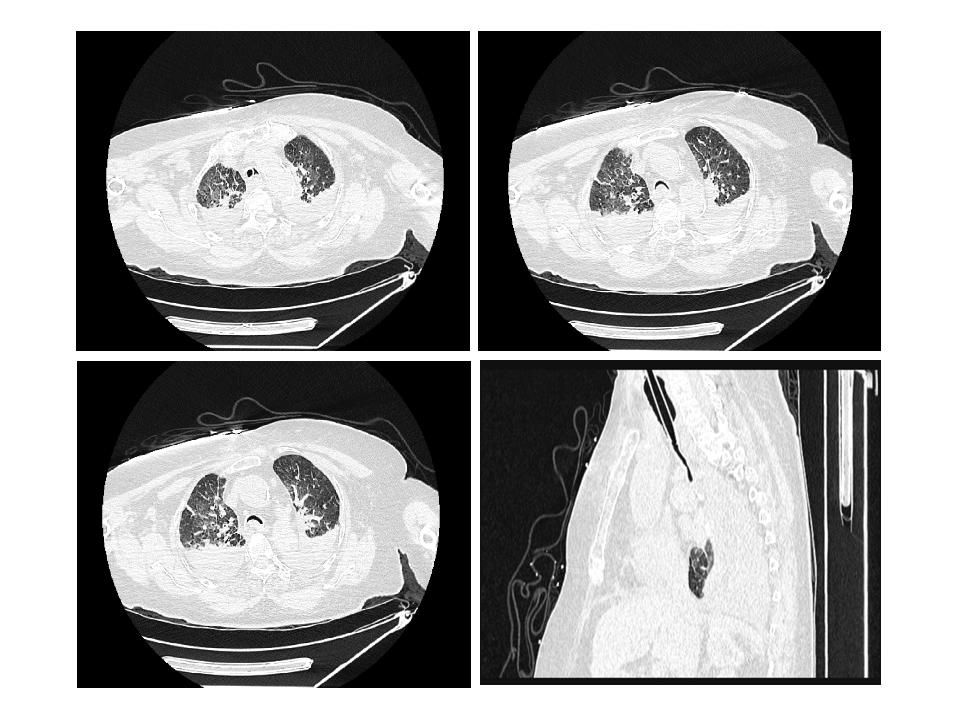

第二次就诊(2020年12月28日):因“突发气促伴意识不清10 min”呼叫120。到达现场时,患者无反应,口唇发绀,大动脉搏动消失,无自主呼吸,血压测不出,立即施行胸外按压、开放气道、球囊面罩通气、开放静脉通道,静注肾上腺素等抢救措施,心电图呈一直线,抢救约10 min后监测显示心电恢复,无颈动脉搏动及自主呼吸,予持续胸外按压、气管插管机械通气,转运至我院急诊。血常规:白细胞13.72×109/L,中性粒细胞百分比44.1%,肌钙蛋白Ⅰ 0.02 ng/mL,血钾5.3 mmol/L,钠138 mmol/L,血酮体0.12 mmol/L,D-二聚体33.88 mg/L,NT-pro BNP 1 204 pg/mL,高敏肌钙蛋白T 29 pg/mL。头颅及胸部CT平扫(图 2)示:(1)脑实质密度减低,脑实质肿胀,不除外脑水肿可能;(2)双侧椎动脉、颈内动脉颅内段硬化;(3)气管、主支气管及其分支退变,气管及双侧主支气管塌陷;(4)双肺慢性支气管炎,双肺多发间质性炎症,双侧胸腔少量积液,较前增多。复苏后心电图示窦性心律,心率98次/min。诊断呼吸心搏骤停、呼吸衰竭、慢性阻塞性肺疾病急性加重期,给予补液、抗感染、机械通气等治疗。至第二天患者家属放弃抢救,宣布死亡。

| 气管导管尖端至隆突段可见显著气管塌陷,膜部向管腔内过度凹陷 图 2 患者第二次就诊(2020-12-29)胸部CT平扫及三维重建图 |